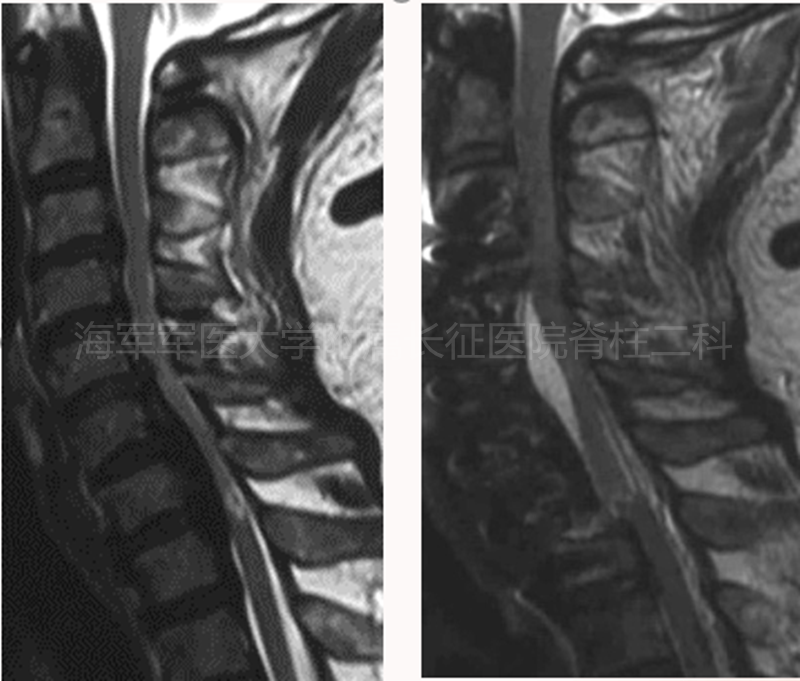

术前MRI

术后MRI